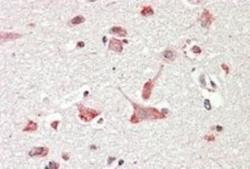

Supportive validation

- Submitted by

- Novus Biologicals (provider)

- Main image

- Experimental details

- Immunohistochemistry-Paraffin: GOLGA6 Antibody [NB100-2436] - Paraffin embedded Human Cerebral Cortex. Steamed antigen retrieval with citrate buffer pH 6, AP-staining.